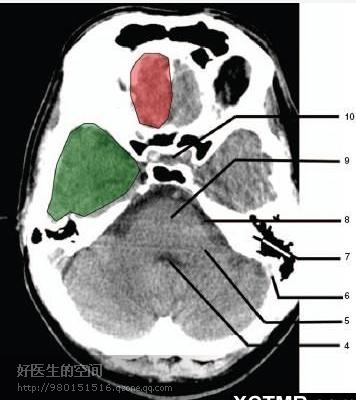

4、第四脑室(Fourth ventricle) 5、小脑中角(Middle cerebellar peduncle) 6、乙状窦(Sigmoid sinus) 7、颞骨及乳突气房 (Petrous temporal bone and mastoid air cells) 8、桥小脑角(Cerebellopontine angle) 9、脑桥 (Pons) 10、垂体窝(Pituitary fossa) 绿色部分为颞叶(Temporal Lobe),浅红色部分为额叶(Frontal Lobe)